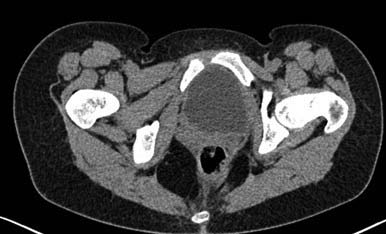

Здравствуйте.Помогите с диагнозом и тактикой лечения.

Больная 15 лет. Жалобы: на укорочение правой нижней конечности, хромоту. Анамнез: Со слов

болеет с детства, травму отрицает. Ранее за медицинской помощью не обращалась. Последние 2

года отмечает резкое укорочение конечности. Локально: При осмотре отмечается умеренное

искривление позвоночника во фронтальной плоскости, умеренная асимметрия лопаток и

надплечий. Скошенность таза. Отмечается укорочение правой нижней конечности на 3 см.

Движения в тазобедренном и коленном суставах в полном объеме. Нейрососудистых нарушений в

периферических отделах нет.